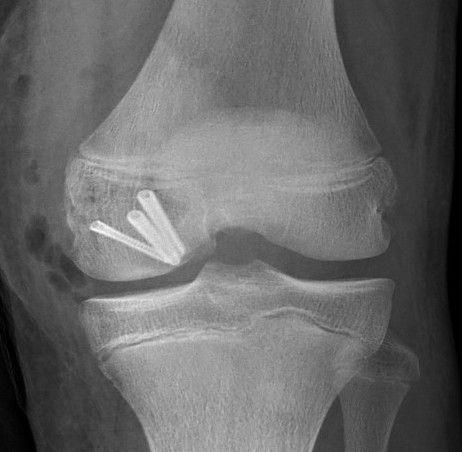

2.  PA screws

Hoffa Fracture ORIF PA screws

3.  Combined

Hoffa fracture